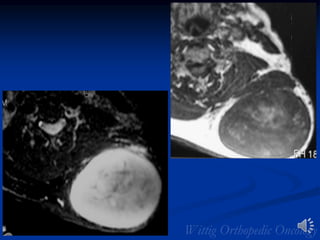

Fibrosarcoma

• MRI

• 2/3 of tumors are intramuscular

• Well defined heterogeneous mass

• Necrosis and hemorrhage are common especially in

higher grade tumors

• Viable areas enhance with contrast; Areas of

significant necrosis and hemorrhage do not enhance

Fibrosarcoma of Right Buttock